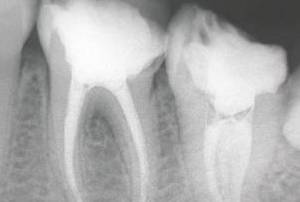

牙齿的稳固是依靠牙龈、牙槽骨、牙周膜、牙骨质等牙周支持组织稳固,一旦其由于各种原因受到破坏,牙齿便会发生松动。

牙周病所引起的牙齿松动

牙周膜长期受到慢性炎症刺激,使牙龈退缩、牙槽骨吸收。这些支持牙齿的牙周组织逐渐破坏后,牙齿就会产生松动现象。

首先,由于牙周组织炎症所引起的牙齿松动是最为常见的,而大部分牙周病的起因是日常清洁做得不到位,其中 牙结石 便是造成牙齿松动的最大凶手之一。

牙结石堆积越多,会向牙颈部位继续进展。时间一长,从牙冠逐渐向下蔓延,牙结石进展一些,牙槽骨就萎缩一些,牙齿就松一些。久而久之,牙齿会逐渐松动,牙结石就会慢慢蔓延到牙根部位!